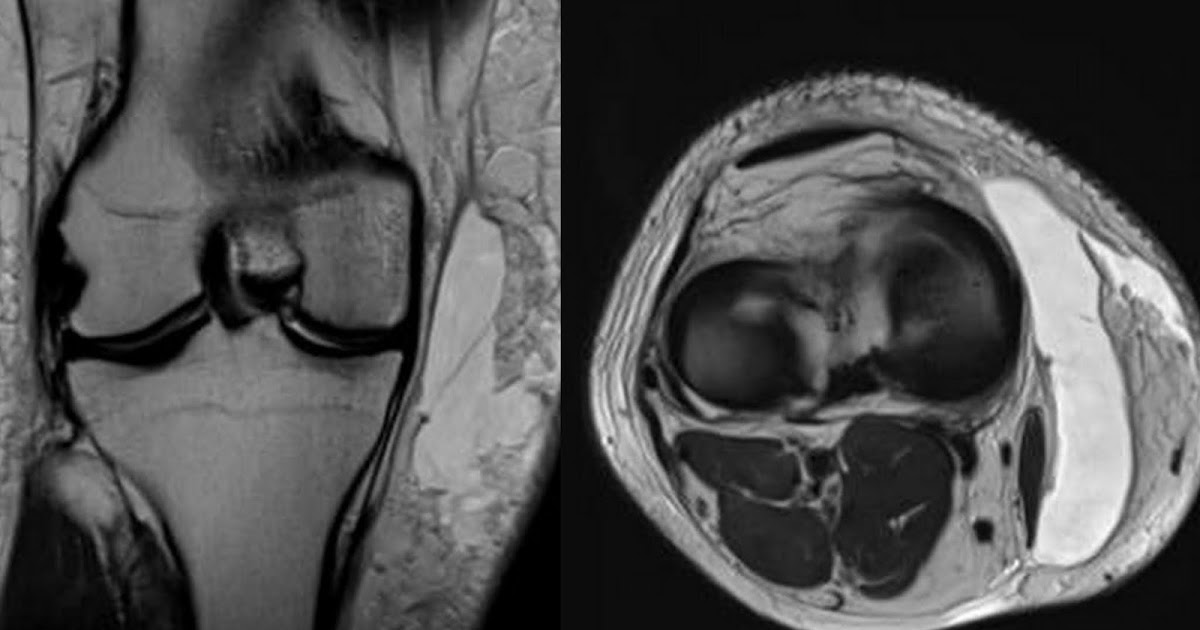

Dr Balaji Anvekar FRCR MorelLavallée lesion MRI

MorelLavallée Lesions of the Knee MRI Findings Compared With Morel Lavallee Lesion Buttock surgical interventions such as open debridement, techniques to close dead space, negative pressure wound therapy,. morel‐lavallée lesion is a closed soft tissue degloving injury usually associated with high‐velocity trauma. Mll occurs most commonly over the greater trochanter (>60% of cases) [1] [3] [5] [6] [8] [11], proximal femur [1] [2] [5], buttock [2] [3] [5], knee [3] [5]. Morel Lavallee Lesion Buttock.

Dr Balaji Anvekar FRCR MorelLavallée lesion MRI Morel Lavallee Lesion Buttock surgical interventions such as open debridement, techniques to close dead space, negative pressure wound therapy,. morel‐lavallée lesion is a closed soft tissue degloving injury usually associated with high‐velocity trauma. The thigh, hip, and pelvic region are the most. It can also occur at the scapula [2] [6]. Mll occurs most commonly over the greater trochanter (>60% of cases). Morel Lavallee Lesion Buttock.

MorelLavallée Lesions of the Knee MRI Findings Compared With Morel Lavallee Lesion Buttock It can also occur at the scapula [2] [6]. morel‐lavallée lesion is a closed soft tissue degloving injury usually associated with high‐velocity trauma. Mll occurs most commonly over the greater trochanter (>60% of cases) [1] [3] [5] [6] [8] [11], proximal femur [1] [2] [5], buttock [2] [3] [5], knee [3] [5] [6] [11] and in rare cases, the. Morel Lavallee Lesion Buttock.